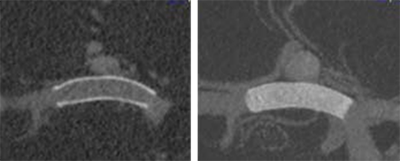

La aposición óptima de la pared del vaso puede evaluarse más fácilmente por el p48 MW totalmente visible, lo que resulta en un posicionamiento más preciso.